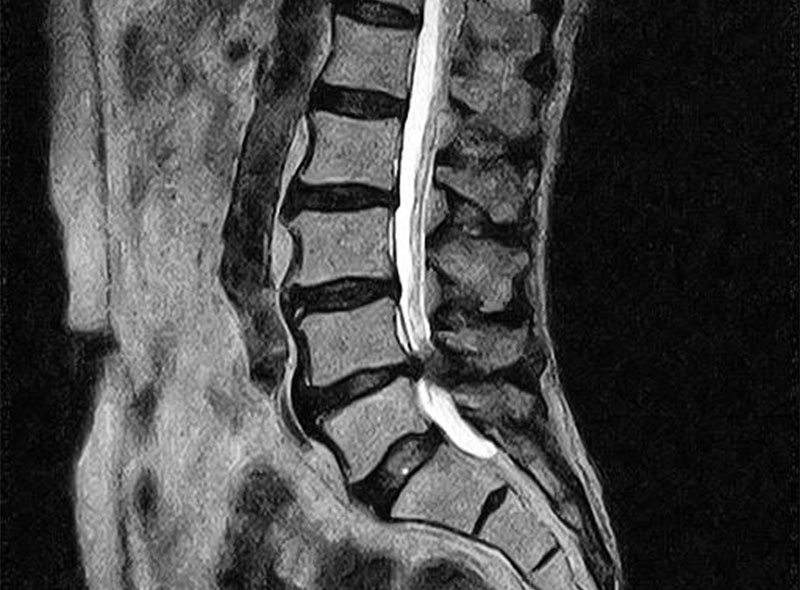

MRI

レントゲンでは判別困難な筋肉、靭帯などの軟部組織や微少骨折などの診断が放射線の被曝無しに行えるため安全で正確な検査が可能です。

当院の機器は開放型MRIであるため検査中の閉塞感が少なくなっています。

腰(脊柱管狭窄症)